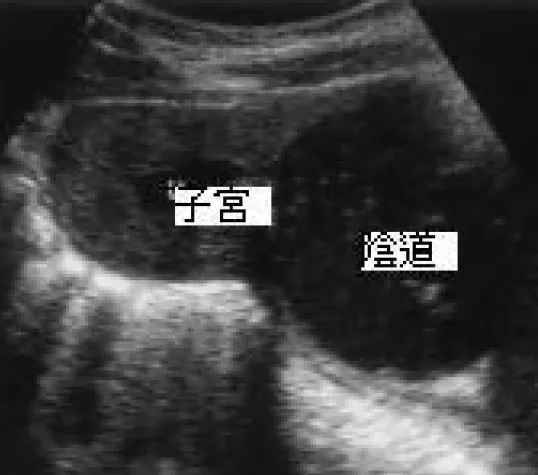

詳解

破題關鍵

這題的解題核心在於辨識超音波影像中的「陰道積血」(hematocolpos),並結合病患有週期性腹痛但無初經的症狀,判斷是生殖道出口阻塞,因此催經治療是無效且不適當的。

選項拆解

登入查看完整詳解與互動作答